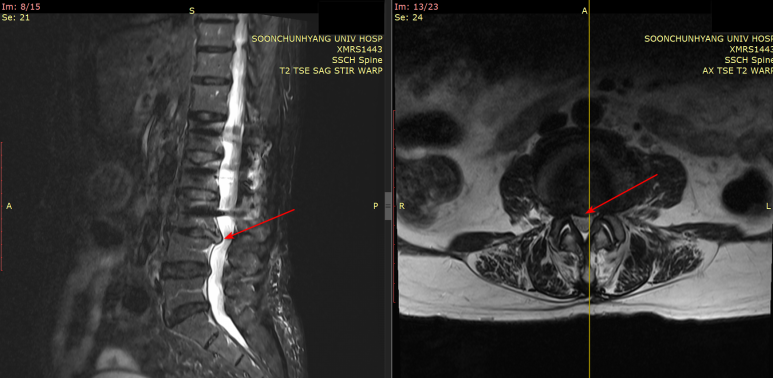

안녕하세요​대한한의영상학회 교육이사안태석 원장입니다​​저는 12년간 경혈 초음파를 활용하며정확하고 효과적으로도침과 약침을 시술하는임상 초음파 연구자입니다.​​​오늘 소개해드릴 치료 케이스는​허리 디스크 치료할 때한번쯤 확인해봐야 할 내용입니다​​디스크가 아닌<다른 질환>은 아닌지​딱 3분만 집중해서 읽어보시길 바랍니다. ​​​ 허리 디스크 탈출증 환자,이번